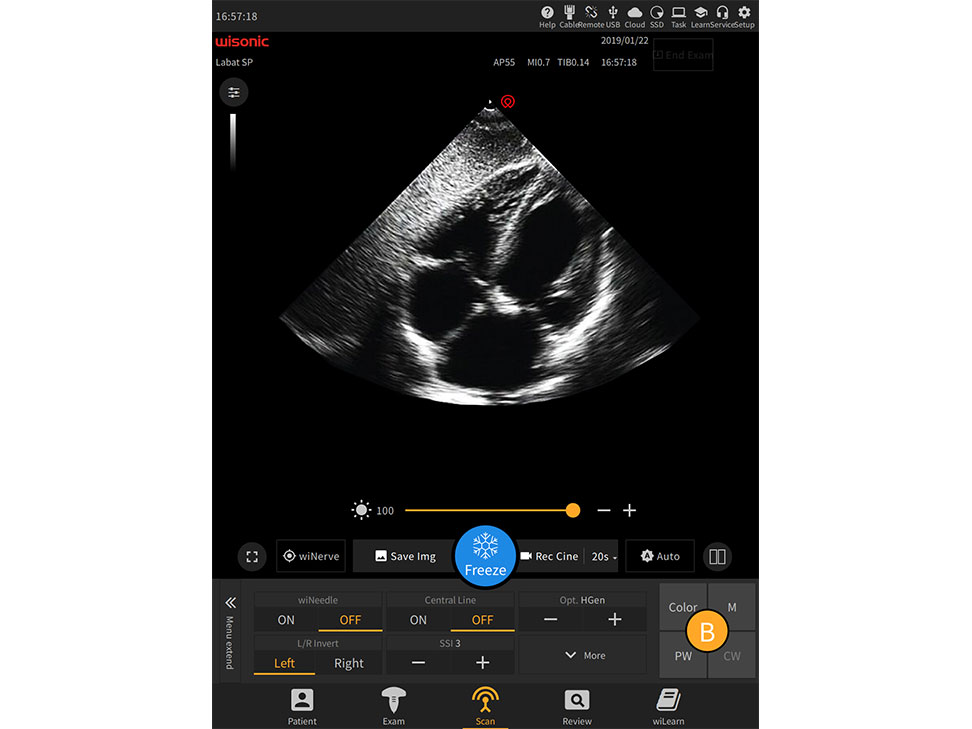

Application pictures